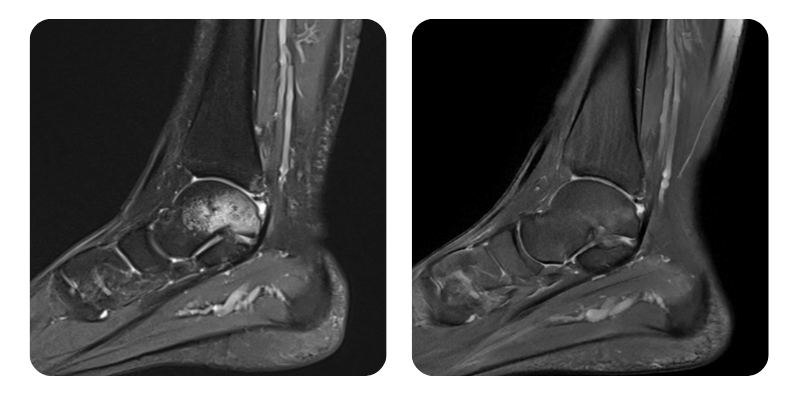

Prima

Dopo

B.A.A., 25 anni - Edema osseo post-contusivo a livello del talo sinistro.

Diagnosi: Edema osseo post-contusivo a livello del talo sinistro, calcagno sinistro, cuboide sinistro e regione malleolare mediale e laterale sinistra; rottura del legamento talo-fibulare anteriore sinistro; edema del legamento talo-fibulare posteriore e della porzione profonda del legamento deltoideo; idrartrosi.

Evoluzione: Si è osservata una riduzione dell'edema di circa il 90%.